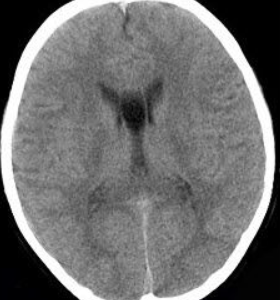

透明隔囊肿ct图片

透明隔间腔与透明隔囊肿鉴别及诊断标准